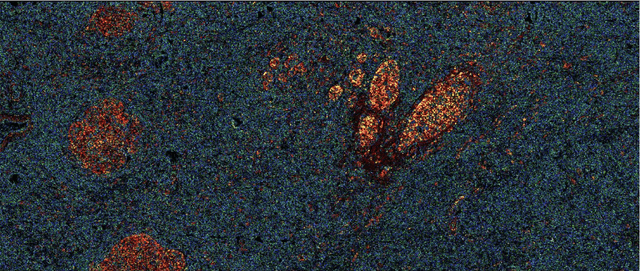

Abstract:Many measurement modalities which perform imaging by probing an object pixel-by-pixel, such as via Photoacoustic Microscopy, produce a multi-dimensional feature (typically a time-domain signal) at each pixel. In principle, the many degrees of freedom in the time-domain signal would admit the possibility of significant multi-modal information being implicitly present, much more than a single scalar "brightness", regarding the underlying targets being observed. However, the measured signal is neither a weighted-sum of basis functions (such as principal components) nor one of a set of prototypes (K-means), which has motivated the novel clustering method proposed here, capable of learning centroids (signal shapes) that are related to the underlying, albeit unknown, target characteristics in a scalable and noise-robust manner.

Abstract:In the past decades, absorption modalities have emerged as powerful tools for label-free functional and structural imaging of cells and tissues. Many biomolecules present unique absorption spectra providing chromophore-specific information on properties such as chemical bonding, and sample composition. As chromophores absorb photons the absorbed energy is emitted as photons (radiative relaxation) or converted to heat and under specific conditions pressure (non-radiative relaxation). Modalities like fluorescence microscopy may capture radiative relaxation to provide contrast, while modalities like photoacoustic microscopy may leverage non-radiative heat and pressures. Here we show an all-optical non-contact total-absorption photoacoustic remote sensing (TA-PARS) microscope, which can capture both radiative and non-radiative absorption effects in a single acquisition. The TA-PARS yields an absorption metric proposed as the quantum efficiency ratio (QER), which visualizes a biomolecules proportional radiative and non-radiative absorption response. The TA-PARS provides label-free visualization of a range of biomolecules enabling convincing analogues to traditional histochemical staining of tissues, effectively providing label-free Hematoxylin and Eosin (H&E)-like visualizations. These findings represent the establishment of an effective all-optical non-contact total-absorption microscope for label-free inspection of biological media.

Abstract:Accurate and fast histological staining is crucial in histopathology, impacting diagnostic precision and reliability. Traditional staining methods are time-consuming and subjective, causing delays in diagnosis. Digital pathology plays a vital role in advancing and optimizing histology processes to improve efficiency and reduce turnaround times. This study introduces a novel deep learning-based framework for virtual histological staining using photon absorption remote sensing (PARS) images. By extracting features from PARS time-resolved signals using a variant of the K-means method, valuable multi-modal information is captured. The proposed multi-channel cycleGAN (MC-GAN) model expands on the traditional cycleGAN framework, allowing the inclusion of additional features. Experimental results reveal that specific combinations of features outperform the conventional channels by improving the labeling of tissue structures prior to model training. Applied to human skin and mouse brain tissue, the results underscore the significance of choosing the optimal combination of features, as it reveals a substantial visual and quantitative concurrence between the virtually stained and the gold standard chemically stained hematoxylin and eosin (H&E) images, surpassing the performance of other feature combinations. Accurate virtual staining is valuable for reliable diagnostic information, aiding pathologists in disease classification, grading, and treatment planning. This study aims to advance label-free histological imaging and opens doors for intraoperative microscopy applications.